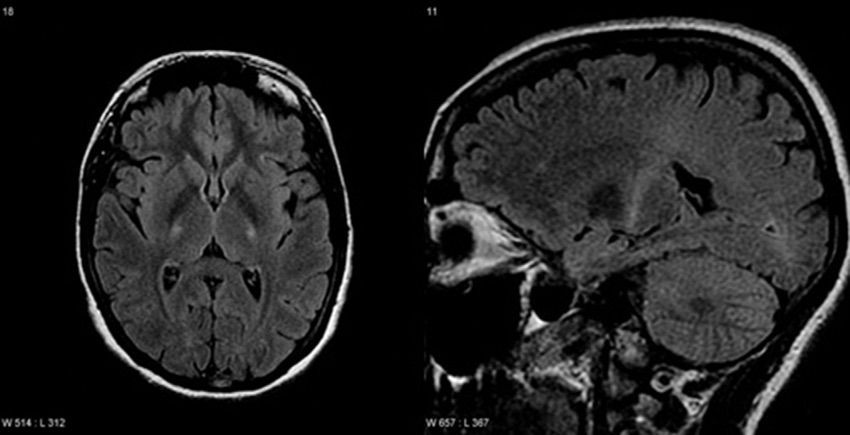

Amyotrophic lateral sclerosis

T2 FLAIR depicting the corticospinal tract degeneration in ALS.